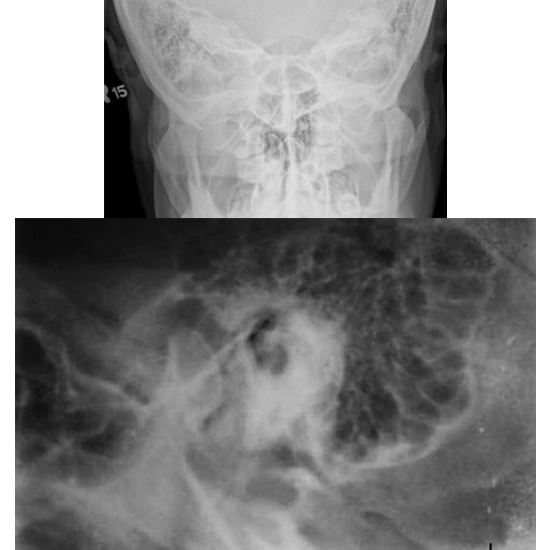

x-ray mastoid lateral oblique and townes view

X-Ray Mastoid Lateral Oblique & Townes View

What is an X-ray Mastoids LAT Oblique & Townes View Test?

The Mastoid X-ray exam is used to visualize the mastoid, a skull bone located directly behind the ear. This bone is composed of air-filled cavities and cells that aid in ear drainage and cleansing.